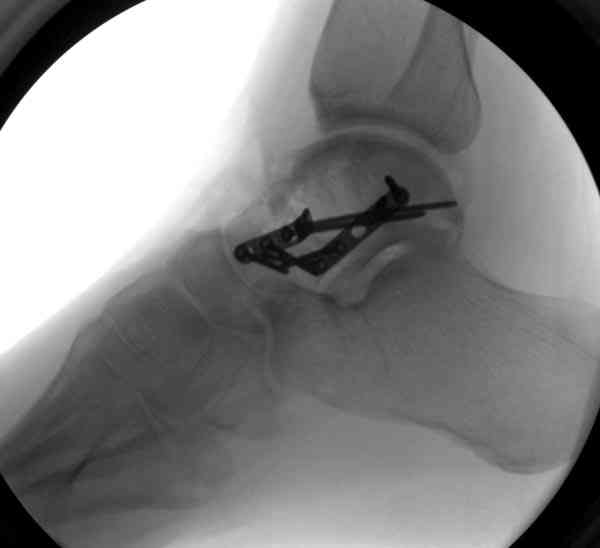

Случай с множественным оскольчатым переломом тарана оперированный из двойного доступа.

Через 2 мес.:

Через 8 мес.:

Через 14 мес.:

Два фрагмента суставной поверхности тарана можно восстановить боковой компрессией шурупами и дополнительно костная пластика.

(кстати, на нашем случае была применена костная пластика-allograft crouton для заполнения дефектов)

Наружный фиксатор "голень-пятка", "лигаментотаксис" при поступлении, домой через 48 часов после обучения ходьбы на костылях, в течение ближайшего времени осмотр в поликлинике для определения кондиции мягких ткани (тест на образование морщин в зоне разреза), при отсутствии отека примерно на 6-7 день с момента травмы операция.

Нагрузку можно разрешить через 2,5 месяца, на конечность снимаемый брейс удобен для разработки сустава которую можно начать после первичной перевязки.

Это примерная тактика при лечении переломов тарана.